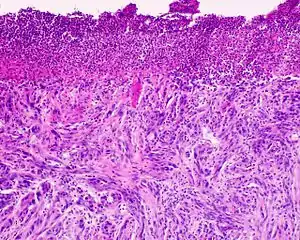

Desmoplastic melanoma

Desmoplastic melanoma is a rare cutaneous condition characterized by a deeply infiltrating type of melanoma[2]:696 with an abundance of fibrous matrix.[3] It usually occurs in the head and neck region of older people with sun-damaged skin.[3] Diagnosis can be difficult as it has a similar appearance to sclerosing melanocytic nevi as well as some nonmelanocytic skin lesions such as scars, fibromas, or cysts.[3]